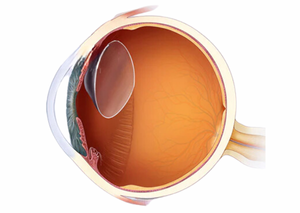

Вітреоретинальна хірургія є спеціалізованим напрямом офтальмологічної хірургії, який фокусується на лікуванні захворювань сітківки та склистого тіла. Цей вид хірургії включає в себе ряд складних операцій, які вимагають високої кваліфікації та сучасного обладнання. У Львів Медікал Центрі застосовуються передові методи вітреоретинальної хірургії для лікування різноманітних захворювань очей, забезпечуючи пацієнтам якісне відновлення зору.

Вітреоретинальна хірургія включає в себе різні хірургічні методи, спрямовані на лікування захворювань сітківки та склистого тіла. Ці процедури можуть бути необхідні при таких станах, як відшарування сітківки, макулярні дірки, епіретинальні мембрани, діабетична ретинопатія та інші складні захворювання очей.

Закрита вітректомія — це мікрохірургічна процедура, яка використовується для лікування захворювань та пошкоджень сітківки і скловидного тіла ока. Вона відноситься до видів операцій на задньому відділі ока.

Ревізія вітреоретинальної порожнини — це хірургічна процедура, яка виконується для огляду та лікування патологічних станів у порожнині ока, що включає скловидне тіло (вітреум) та сітківку (ретину).